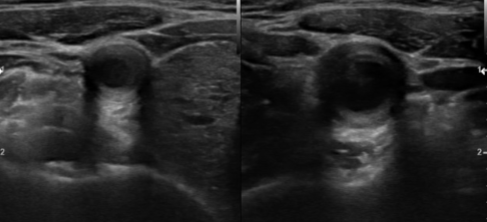

What pathology is seen here?

Temporal Arteritis

What is the key sonographic feature of Temporal Arteritis?

Anechoic halo around the vessel lumen

List the 2 sonographic findings of Temporal Arteritis.

Narrowed segment of the vessel

Anechoic halo around the vessel lumen secondary to edema

The anechoic halo seen on Temporal Arteritis is secondary to what other pathology?

Edema